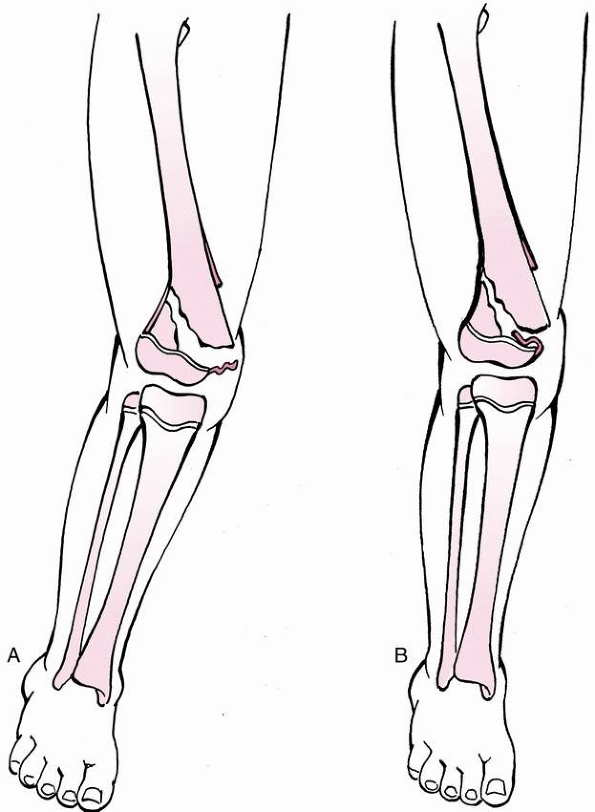

FIGURE 23-2 Valgus and torsional stress across the knee may cause a ligament injury or physeal separation.

FIGURE 23-3 A. In a skeletally mature patient with closed physis, tensile failure usually occurs across the ligament. B.

In a skeletally immature patient with open physis, failure usually occurs across the physis. (Reprinted with permission from Skaggs DL, Flynn JF. Trauma about the knee, tibia, and foot. In Skaggs DL, Flynn JF, eds. Staying out of Trouble in Pediatric Orthopaedics. Philadelphia: Lippincott Williams & Wilkins; 2006.) |